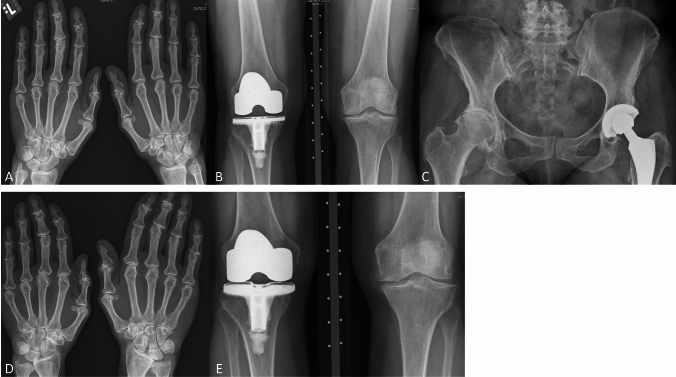

Despite achievement of biochemical remission, she had progressive, joint pain and stiffness in the hands, knees, hips, shoulders, ankles, and feet—varying in intensity depending on the joint. The joint complaints negatively influenced her daily functioning, with walking for over 15 min becoming impossible, resulting in the need for gait aids for long distances, pain medication, and physiotherapy, although she did not experience any beneficial effect of physiotherapy. Prior to retirement, she could work for 6 h a week. She was, however, able to bike and swim (non-weight-bearing exercise) without noticeable limitations. Radiographically, significant progression of structural abnormalities with end-stage arthropathy at multiple joint sites, as shown in Fig. 2, was observed. She received repetitive steroid injections in the left knee, followed by a 4th large joint prosthesis (total left knee prosthesis) in May of 2022.

Fig. 2.

Radiographic examination of the hands, knees, and hips with follow-up. The first detailed radiographic examination of the joint complaints occurred in 2010 (A, B, C), with a follow-up detailed examination in 2016 (D, E). A Dorsovolar radiograph of the hands. Osteoarthritis of the hands, predominantly in the interphalangeal joints but also in other joints such as the MCP joints. B Posteroanterior radiograph of the knees. Osteoarthritis in the left knee, total knee replacement in the right knee. C Anteroposterior radiograph of the pelvis. Severe osteoarthritis in the right hip, total hip replacement on the left side. D Follow-up dorsovolar radiograph of the hands. Progression of the osteoarthritis in the hands, predominantly in the interphalangeal and MCP joints but also in other joints. E Follow-up posteroanterior radiograph of the knees. Progression of the osteoarthritis in the left knee